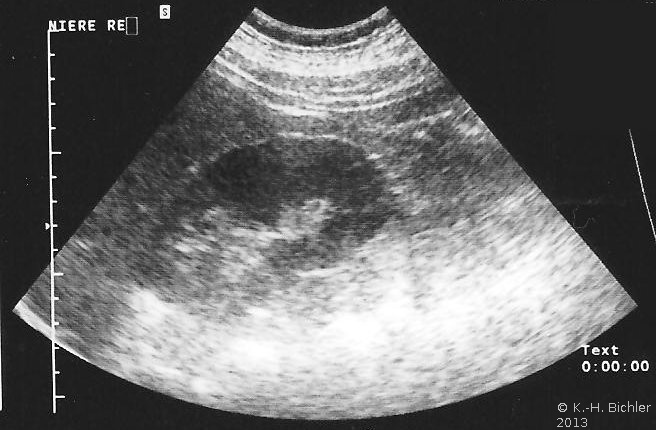

In der Sonographie fand sich eine kleine Niere links bei unauffälliger rechter Niere (Abbildung 18b).